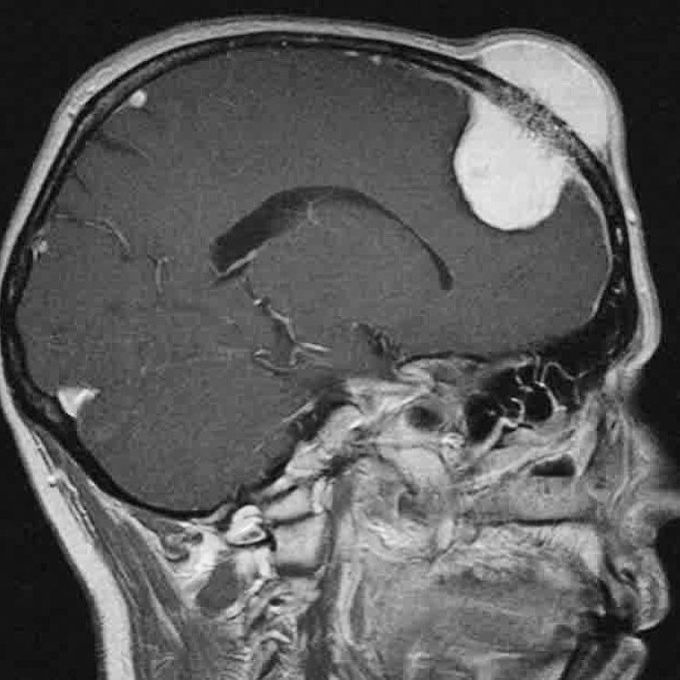

These are rare bone (osseous) tumors that constitute less than 1% of all bone tumors. They're classified as benign, slow-growing tumors of vascular nature (hence the name hemangioma), that originate and expand inside bone structures. Although found in any bone, seventy-five percent of intraosseous hemangiomas are located in the vertebral bodies (especially the thoracic spine), skull (involved outer table, normal inner table), and facial bones. Vertebral body hemangiomas are usually asymptomatic and left untreated. Sometimes they are incidentally found in a patient with low back pain. They may develop a soft tissue mass which may lead to neurologic symptoms like pain and numbness. A CT or MRI is used to diagnose and define the epidural extent.Photo credit : @brainpage